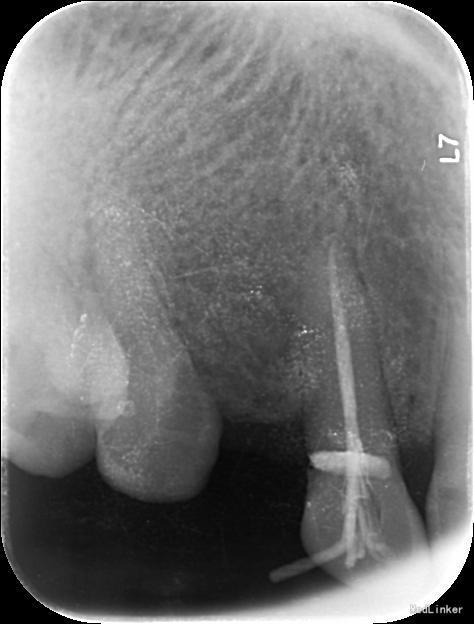

诊断:13慢性根尖周炎 治疗计划:13根管治疗后冠修复 治疗:1. 13去腐,腭侧开髓暴露髓腔,降牙合,探查根管,干燥根管,电测工作长度WL=25mm,此时根尖区探痛明显,按此长度插针拍片示超出根尖孔4mm,推算出WL=21mm。EDTA下,常规预备至35#,3%过氧化氢和生理盐水冲洗+超声荡洗根管交替进行。隔湿,干燥根管,封CP棉球, 氧化锌水门汀暂封。嘱勿用患牙咬物。 2.主诉:右上前牙上次治疗后后无不适。 检查:13暂封物在,叩痛(-),牙体无松动,牙龈未见明显异常。 处置:13去除暂封物,生理盐水冲洗并干燥根管,试尖到位,进口根充糊剂+牙胶尖冷侧压根管充填,氧化锌水门汀暂封,术后拍片示:13根充恰填。嘱勿用患牙咬物。 建议:13冠修复

根管治疗的关键是彻底清洁根管系统,对根管进行严密的充填,根管充填的止点是根尖狭窄处,即牙本骨质界,此处是解剖学和组织学牙髓末端及牙周组织的起始点,器械一旦超出牙本骨质界,就会对根尖周组织造成创伤,并将炎症带入根尖周组织。因此,在根管预备前,准确测定工作长度非常重要。 工作长度是指从牙尖至牙本骨质界之间的距离,它不同于牙的长度。 牙长度为切缘或牙尖至解剖根尖之间的距离。 临床上常用的方法有电测法、X 线辅助计算法,根尖定位仪借助于根管内部阻抗的规律性变化对其工作长度进行测量,准确性强,且应用简单方便,能够对根尖已经完成发育的牙根准确的测定其根管工作长度。但该方法亦具有一定局限性,如对戴有心脏起搏器患者严禁应用,同时期准确性也会因根管内外某些因素而受到干扰。X 线辅助测量通过将根管及根尖区域进行二维成像,在平面影像上确定根管长度,但这种平面影像只能分辨牙本质- 骨质界,而当根尖区不清晰时则无法准确判断根尖狭窄所在。同时这种方法测量准确性与拍摄技术、选用方法均有一定关系。 本病例先是通过根尖定位仪测量工作长度,但是在根尖定位仪显示至根尖狭窄时,长度为25mm,此时患者疼痛明显,按此长度摄插针X片,显示超出根尖孔4mm,推测出实际工作长度为21mm,按此长度预备后根管充填显示恰填。分析电测法出现误差的原因可能有两种,一是牙齿颈部的重度楔状缺损以及电解液的冲洗等可导致测量电流发生颈漏, 而使测量值不准确;二是由于根尖区牙槽骨受到破坏而导致骨小梁稀疏,锉尖在从根尖孔穿出后无法探及根尖处牙槽骨,而穿出一段距离后与根尖外部牙槽骨相接才形成回路,此时测量仪才会认为探及根尖而显示数值,故所得数值偏大。 目前, 根尖定位仪在临床应用上还是比较稳定的,在大多数的病例中定位根尖止点的准确性较高, 但是也会受到电解质、龈下龋、根折、根尖孔粗大和根尖未成形等因素的影响, 可能会产生错误结果,此时仍然需要X 线摄片的辅助。因此在使用根尖定位仪的过程中要注意, 当遇到一些特殊的情况时, 结合X 线照片法可以提高测量根管工作长度的准确性,此外,X 线片对牙体、牙周等组织情况均可以提供直观的影像,这对临床诊治具有十分重要的作用与意义。